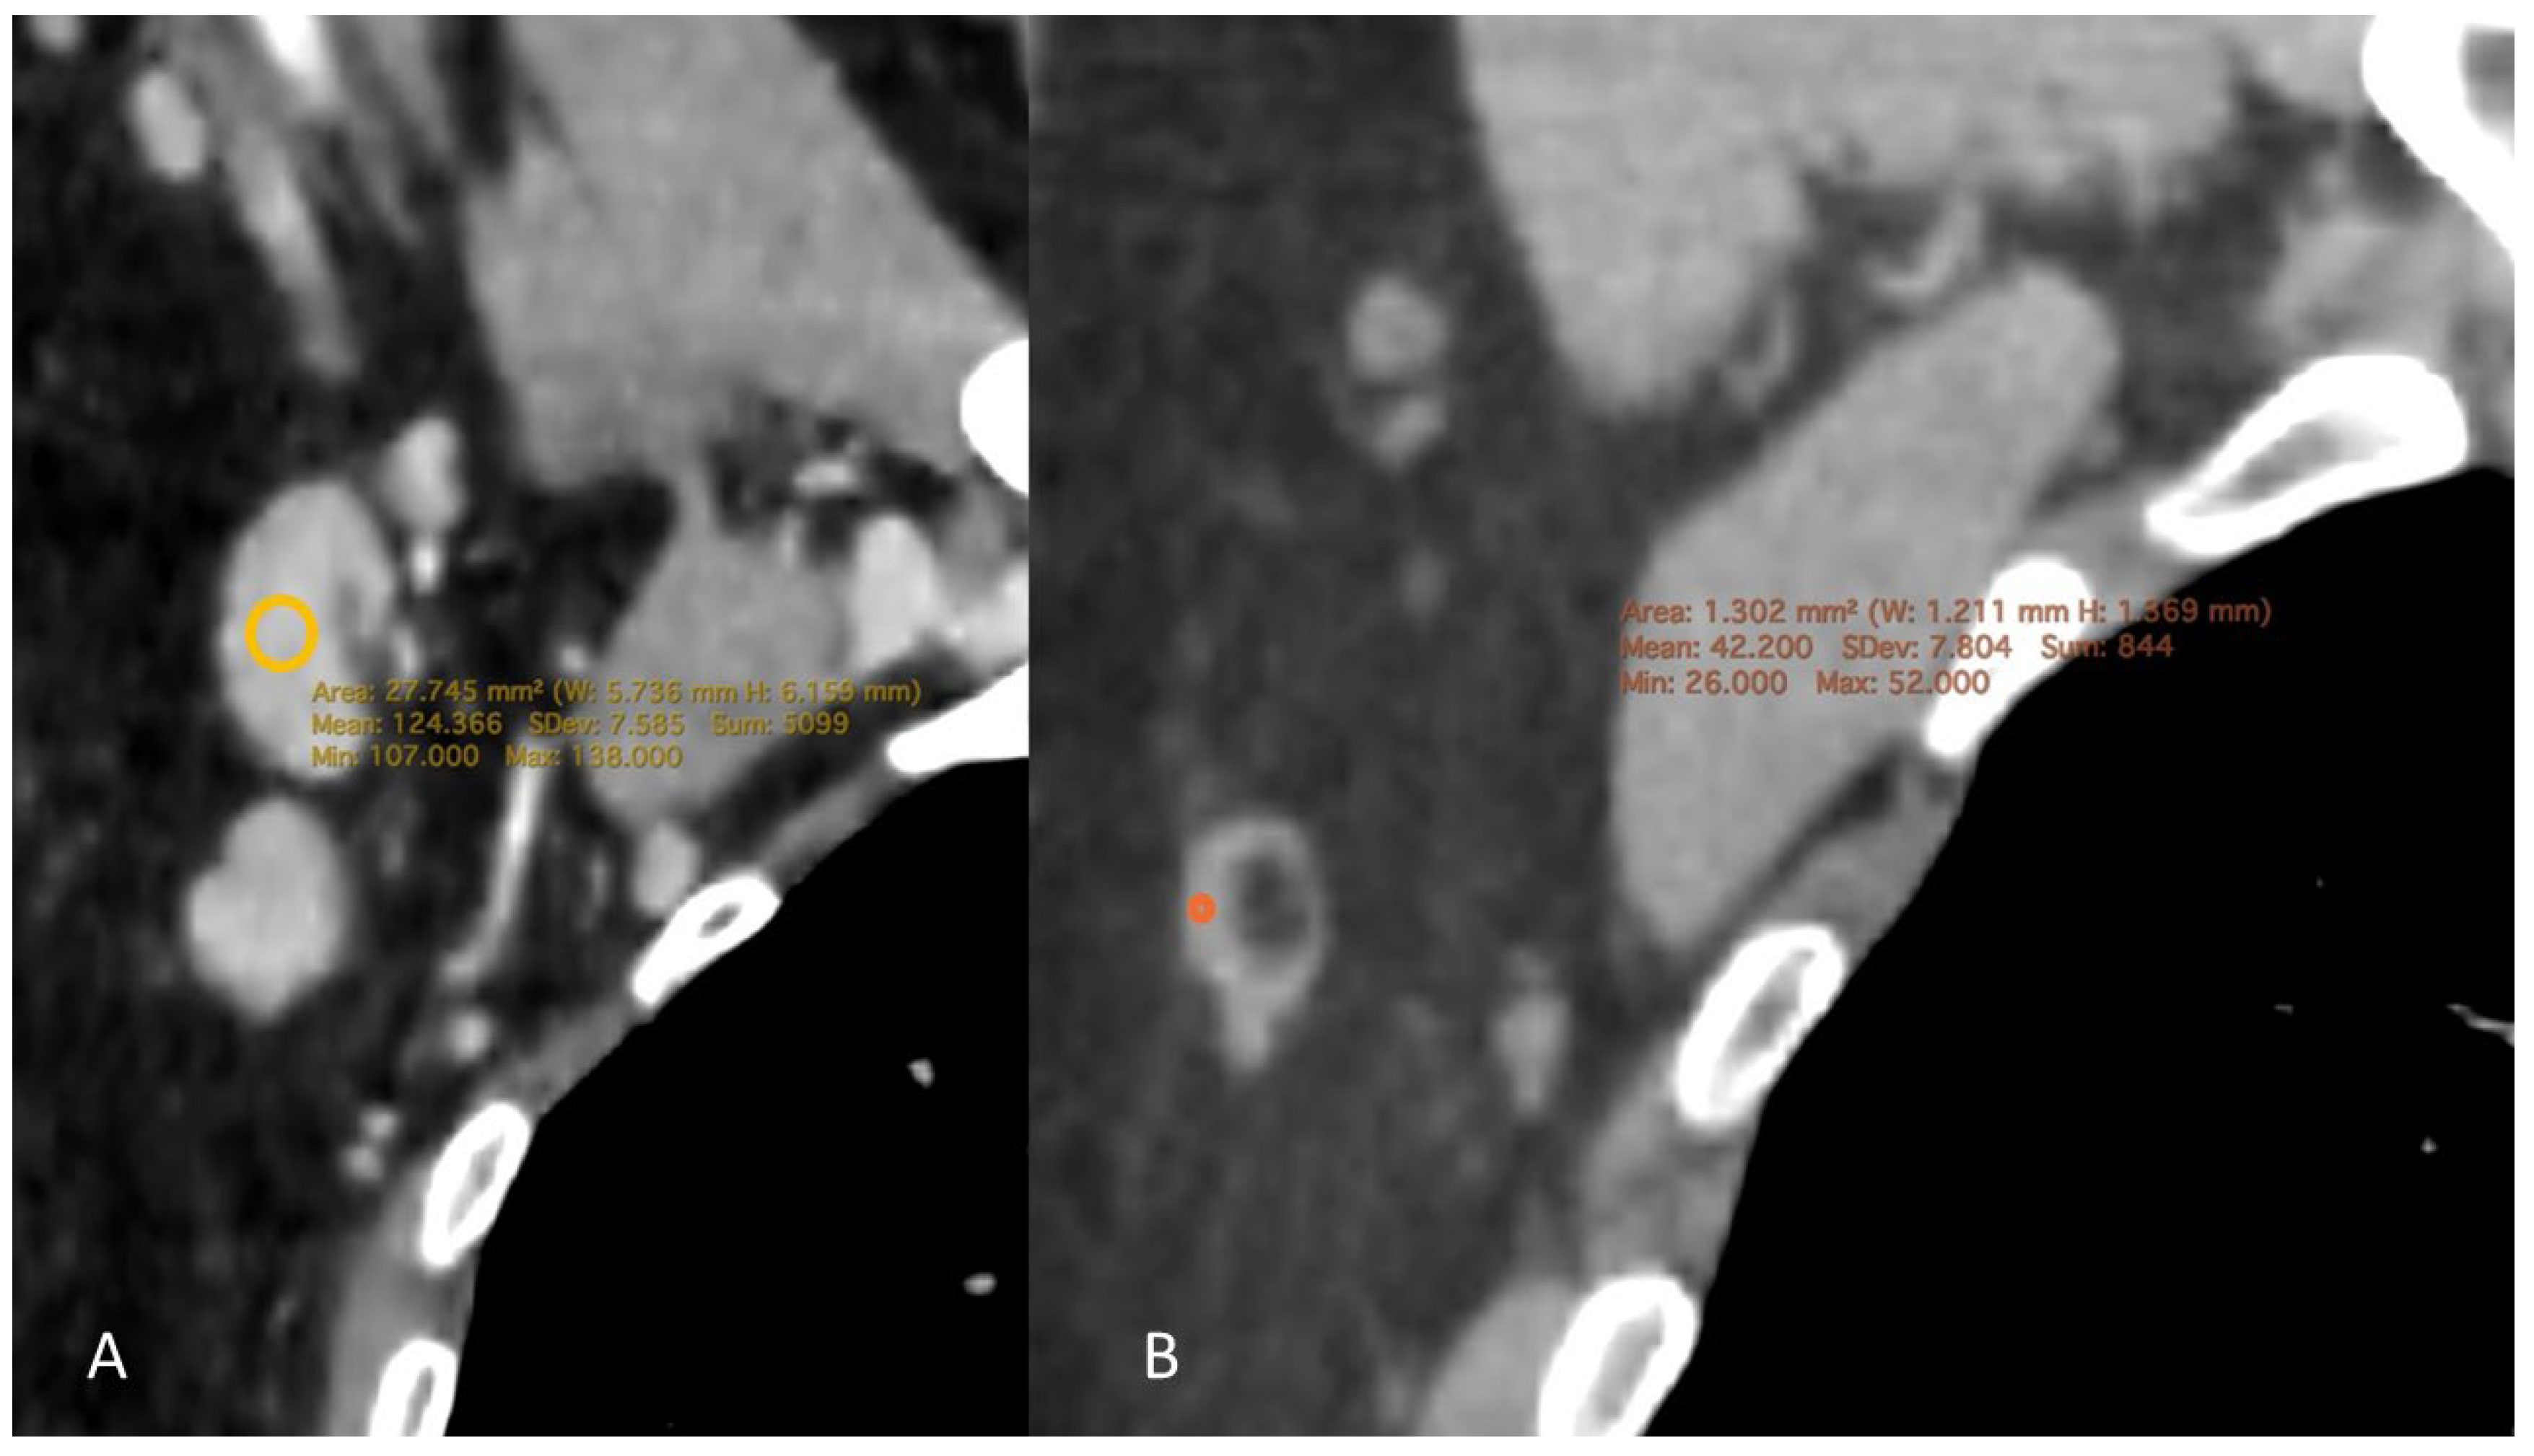

1.4. CT Measurement

2.4. CD4 Count and Density as a Predictor

2.5. Radiological Findings by Viral Load

3. Discussion